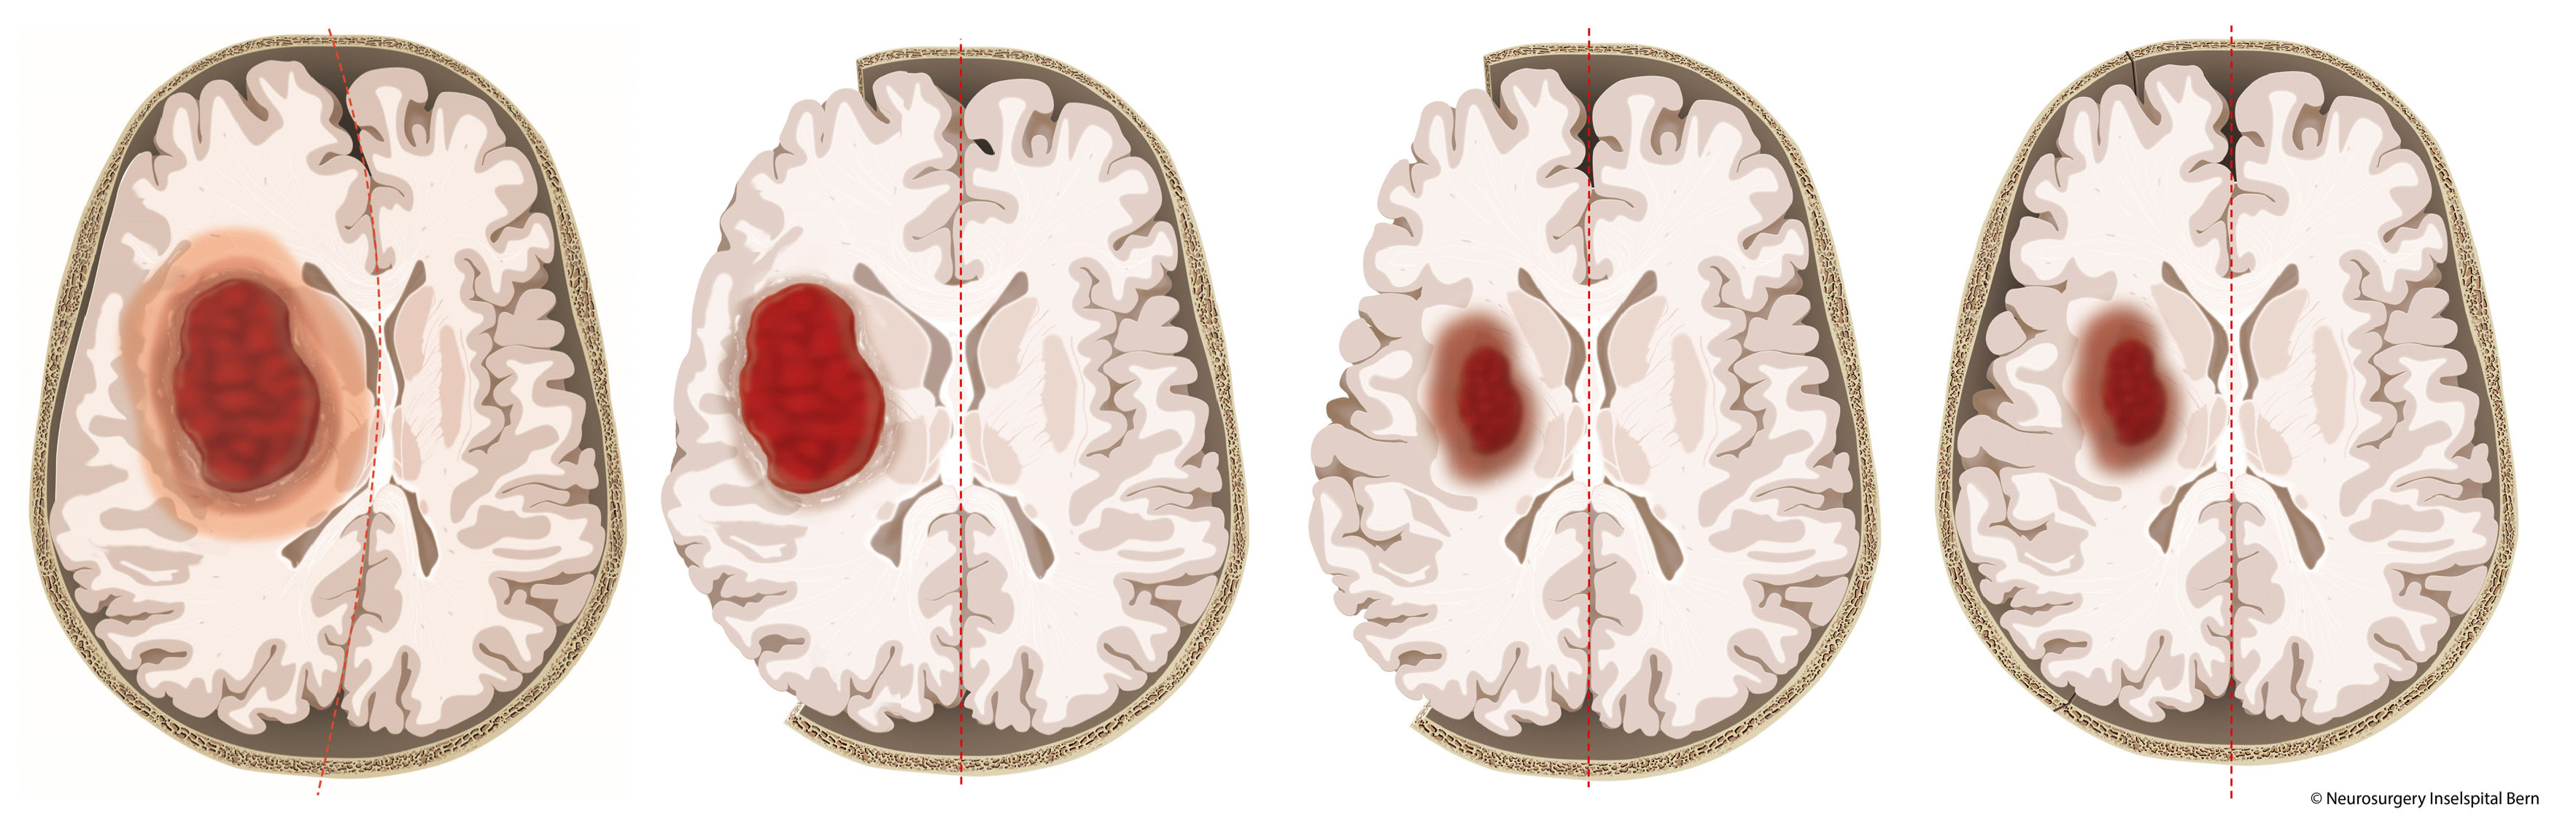

Mehr als 50.000 Menschen in Deutschland erleiden jährlich eine spontane Blutung im Gehirn. Ein solcher hämorrhagischer beziehungsweise blutiger Schlaganfall ist akut lebensgefährlich. Gerade tief im Gehirn liegende Blutungen haben meist massive Konsequenzen. Die Blutung und folgende Schwellungen üben Druck auf das umgebende Gehirngewebe aus und führen so zu weitreichenden Schäden im Gehirn. Eine wirksame Therapie gibt es bislang nicht. Nun gibt es erstmals wertvolle Hinweise auf einen wirksamen neurochirurgischen Ansatz, wie ein internationales Team um Ärzt*innen der Universitätskliniken Freiburg und Bern, Schweiz, zeigt. Sie fanden Hinweise, dass ein Öffnen der Schädeldecke und damit eine Druckminderung im Gehirn zu weniger schweren Verläufen führt Die sogenannte SWITCH-Studie erschien am 15. Mai 2024 im führenden Fachmagazin The Lancet und wurde zeitgleich auf dem Kongress der European Stroke Organisation (ESOC) in Basel vorgestellt.

Blutungen in tiefliegenden Regionen des Gehirns sind für Patient*innen besonders gefährlich. Sie führen oft zu schweren Behinderungen, Pflegebedürftigkeit und hoher Sterblichkeit. Die Behandlungsmöglichkeiten sind derzeit auf blutdrucksenkende und blutungsstillende Medikamente begrenzt und oft nicht ausreichend – eine durch Studien gesichert wirksame Therapie gibt es gar nicht. Gleichzeitig ist die Forschung im Bereich der tiefen Hirnblutungen besonders anspruchsvoll, da die betroffenen Gehirnareale schwer zugänglich sind und Blutungen schnell lebensbedrohlich werden. Bisherige Studien zu verschiedenen Operationsmethoden scheiterten daran, einen klaren Vorteil für Patient*innen zu zeigen.

Die SWITCH-Studie untersuchte daher gezielt die Wirkung einer Kraniektomie zur Druckentlastung bei besonders schwer betroffenen Patient*innen. Dabei wurde ein Teil der Schädeldecke entfernt und nach Rückgang der Schwellung wieder implantiert. Die Patient*Innen erhielten entweder die bisherige Standardtherapie oder die Standardtherapie in Kombination mit der Dekompressions-Kraniektomie.